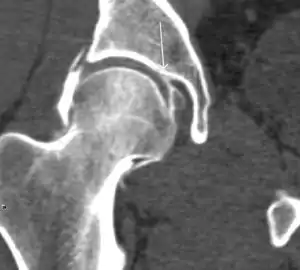

Synovial chondromatosis can be confidently diagnosed by X-ray when calcified cartilaginous chondromas are seen. However, other synovial proliferative processes, such as pigmented villonodular synovitis, require MRI for accurate diagnosis, although noncalcified synovitis can be suspected in radiographs by indirect signs, such as soft tissue swelling and/or erosions in the femoral head, femoral neck, or acetabulum (Figure 7).[1]

Figure 7:

Axial CT image of pigmented villonodular synovitis eroding the posterior cortex of the femoral neck.[1]

Sagittal T2* gradient echo image showing a posterior soft tissue mass with hypointense areas secondary to hemosiderin deposition.[1]

X-ray of synovial chondromatosis.[1]

CT of synovial chondromatosis.[1]

In synovial proliferative disorders, MRI demonstrates synovial hypertrophy. In the case of PVNS, characteristic foci of low signal intensity related to hemosiderin deposition are better seen on gradient echo T2* images (Figure 7). In the case of synovial osteochondromatosis, the synovial hypertrophy is accompanied by intermediate signal cartilaginous loose bodies and/or low signal calcified loose bodies.[1]

Computed Tomography

Due to radiation concerns, CT has been relegated after MRI in the study of intra-articular causes of hip pain. The only exception where CT is considered superior to MRI is in bone tumors, because of its ability in characterizing matrix calcifications, and in depicting the anatomy of acute traumatic fractures. Typical matrix calcifications include the following: (a) osteoid mineralization, like a dense cloud, (b) chondroid calcification, reproducing a punctate popcorn pattern, or (c) fibrous calcification, ground glass-like appearance. There are also tumors that typically do not show matrix calcification. CT is also used for accurate localization of the nidus in osteoid osteomas and this must be differentiated from Brodie’s abscess or a stress fracture. The current standard treatment of osteoid osteoma is percutaneous radiofrequency ablation and this is usually performed under CT guidance.[1]